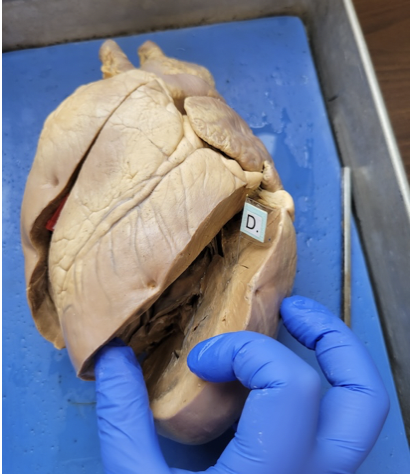

what is this

the left ventricle